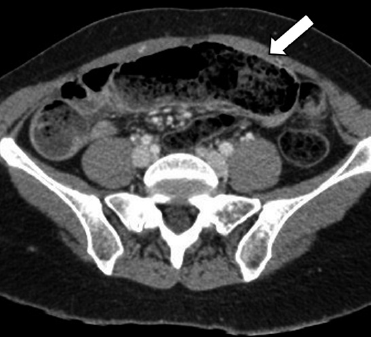

Imagen de portada

Caso clínico: Paciente sexo femenino con antecedente de BGLYR hace 2 años y cuadro de obstrucción intestinal causado por fitobezoar.